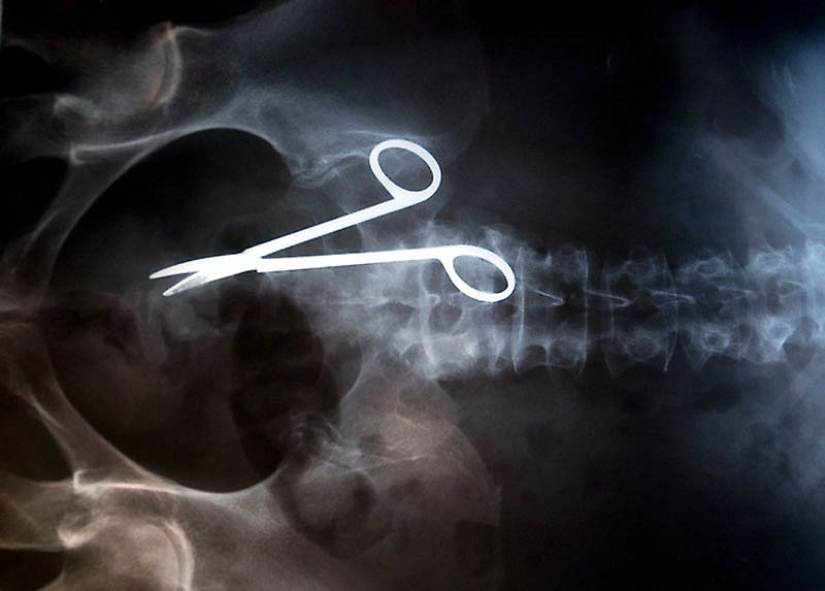

12. Tijeras quirúrgicas dejadas accidentalmente en el cuerpo del paciente después de la cirugía. Las tijeras fueron descubiertas solo 18 meses después de la operación, porque la mujer se quejaba de dolor constante en los intestinos.